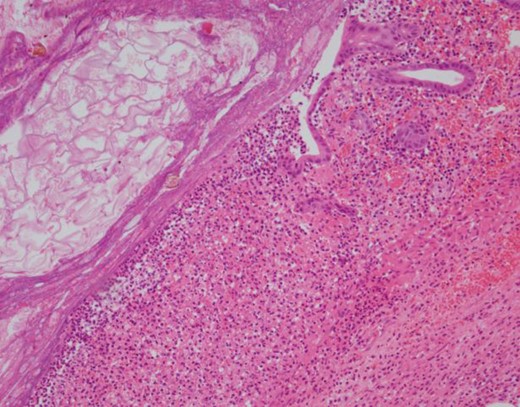

During the exploratory laparotomy, the segment of small bowel with the inflammatory phlegmon was noted and withdrawn from the surgical site for inspection. An isolated segment of bowel measuring ~20 cm was resected between and a side-to-side functional and end anastomosis was created. The surgical findings included a solitary diverticulum at the mesenteric aspect of the bowel with marked erythema, induration and slight exudate at the proximal jejunum. There was no evidence of diverticular perforation. Pathology revealed the serosal surface of the jejunum was notable for a 2.5 cm region of protrusion associated with congestion, exudation and possible hemorrhage; when the resected segment of small bowel was opened, there was a prominent fecal filled diverticulum corresponding to the focus of serosal protrusion (Figs 2–4).

H&E 1× image of the small bowel diverticulum (top of image) pouching out from the bowel lumen (bottom of image).